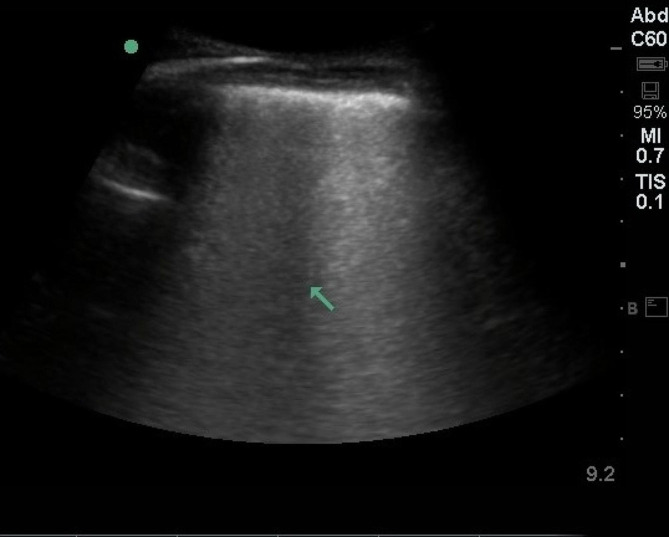

Results: Forty-eight patients (25 women (52%), mean age 75 years, standard deviation (SD) ± 7.7 years) were enrolled in the study. We detected severe B-lines (≥ 30) in 13 (27%) patients and moderate B-lines (15-30) in 33 (68.6%) patients. The number of B-lines increased significantly with the severity of New York Heart Association (NYHA) functional classes (Fig. 1). The B-line count was 14 ± 13 in NYHA class I patients, 20 ± 20 in class II patients, and 44 ± 35 in class III patients (p < 0.05, rho = 0.384). The number of B-lines was correlated with the E/E' ratio (R = 0.664, p < 0.0001) and the proBNP level (R = 0. 882, p < 0.008). We found no significant correlation with the LVEDP or LVEF. The LVEDP correlated well with the E/E' ratio (R = 0.491, p < 0.001) but not at all with E/A, DT, or LAVI. All patients had an elevated LVEDP > 12, with a mean pressure of 26 mmHg, a minimum of 13 mmHg, and a maximum of 45 mmHg, with an SD of 7.85.